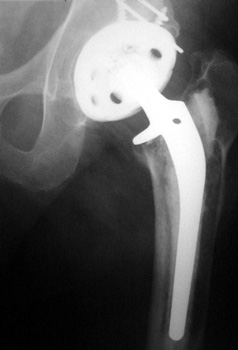

OSTEOLYSIS

Multifocal and massive, involving Gruen zone III of acetabular cup and Grune zone 1,2, and 6 of femoral component

Radiograph and CT